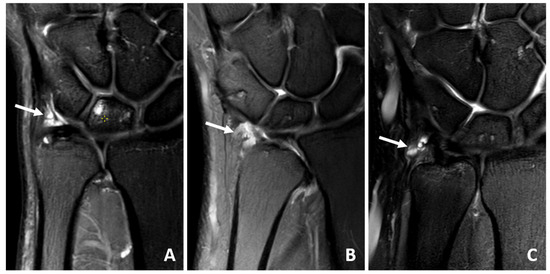

3.4. MRI Scan